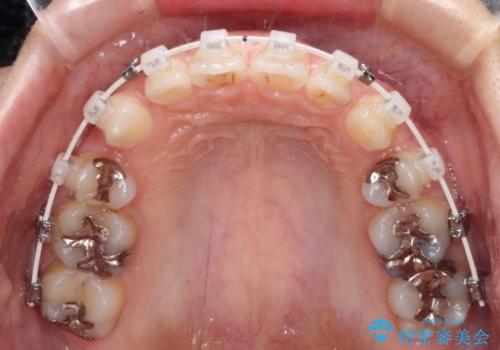

- 審美装置

- 口元の突出感と口の閉じにくさを気にして来院された患者様です。

上下左右第一小臼歯4本を抜歯し、ワイヤー装置にて口元を引っ込めるよう矯正治療を行うこととしました。

奥歯が前方に傾斜していることで深く咬みこむ(ディープバイト)状態であったので、なかなか抜歯したスペースが閉じず、様々な方法でディープバイトを改善しながら治療を進めていくこととなりました。